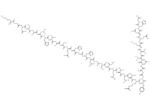

– [C@@H](CC1=CN=CN1)(NC([C@@H](NC([C@@H](NC([C@@H](NC([C@@H](NC(CNC([C@H](CCCCN)N)=O)=O)CC(N)=O)=O)CO)=O)C)=O)CC(C)C)=O)C(N[C@H](C(N[C@H](C(N[C@H](C(N[C@H](C(N[C@@H](CC2=CN=CN2)C(NCC(N[C@@H](CC3=CN=CN3)C(N[C@H](C(NCC(N[C@H](C(N[C@H](C(N[C@H](C(N[C@H](C(N[C@H](C(N[C@H](C(N[C@H](C(N[C@@H](CC4=CC=C(O)C=C4)C(NCC(N[C@H](C(N[C@H](C(N[C@H](C(N[C@H](C(N[C@H](C(N[C@H](C(N[C@H](C(N[C@@H](CC5=CN=CN5)C(NCC(O)=O)=O)=O)CC(N)=O)=O)CCC(N)=O)=O)CCSC)=O)[C@@H](C)O)=O)C(C)C)=O)CC(N)=O)=O)C)=O)=O)=O)CCCNC(=N)N)=O)C(C)C)=O)CC(C)C)=O)[C@@H](C)O)=O)CCC(N)=O)=O)[C@H](CC)C)=O)CS)=O)=O)CC(C)C)=O)=O)=O)=O)CCC(N)=O)=O)CO)=O)C)=O)C(C)C)=O